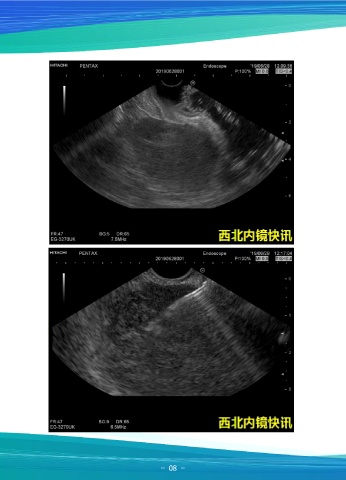

一例十二指肠乳头增生性病变

患者女,50岁,因“间断右上腹疼痛1年”入院,胸部及上腹部CT示:左肺下叶背

段微结节;左肺下叶慢性炎症;肝左叶囊肿;肝右叶钙化灶,右肾囊肿;腹水。